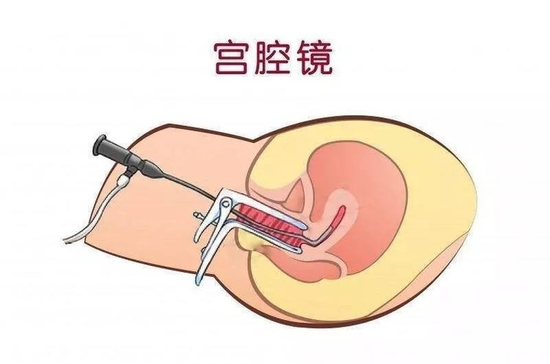

妇产科主任李宇、副主任李晓燕根据患者病情及超声检查结果,经过术前充分讨论,考虑剖宫产切口憩室引起经期延长可能性大,建议行宫腔镜检查,术中备行剖宫产切口憩室修复术。医护人员向患者及家属详细交代病情及可选择的治疗方案,其最终决定上述手术治疗。

经宫腔镜剖宫产切口憩室修复术是目前治疗剖宫产切口憩室的有效方法,患者术后上述症状多有明显改善,部分患者月经恢复正常。该手术利用天然通道,无伤口、失血少、恢复快,是治疗剖宫产切口憩室的最微创手术方法。术中还可同时诊断及治疗其他宫腔病变,为临床所推荐,也易被患者接受。

此次手术由妇产科白帆副主任医师主刀,洪雪玲主治医师协助。由于该手术涉及宫内电操作,且憩室顶部残余肌层薄,紧邻膀胱,憩室空间狭小(10mm3左右),操作稍有疏忽,即可造成子宫穿孔、膀胱损伤。所以要求手术者经验非常丰富,操作极为精准,电切、电凝要恰到好处,属于4级高风险手术,可谓“螺狮壳里做道场”。